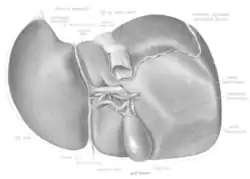

Structure

The liver is a dark reddish brown, wedge-shaped organ with two lobes of unequal size and shape. A human liver normally weighs approximately 1.5 kilograms (3.3 pounds)[9] and has a width of about 15 centimetres (6 inches).[10] There is considerable size variation between individuals, with the standard reference range for men being 970–1,860 grams (2.14–4.10 lb)[11] and for women 600–1,770 g (1.32–3.90 lb).[12] It is both the heaviest internal organ and the largest gland in the human body. It is located in the right upper quadrant of the abdominal cavity, resting just below the diaphragm, to the right of the stomach, and overlying the gallbladder.[5]

Lobes

The liver is grossly divided into two parts when viewed from above – a right and a left lobe – and four parts when viewed from below (left, right, caudate, and quadrate lobes).[14]

The falciform ligament makes a superficial division of the liver into a left and right lobe. From below, the two additional lobes are located between the right and left lobes, one in front of the other. A line can be imagined running from the left of the vena cava and all the way forward to divide the liver and gallbladder into two halves.[15] This line is called Cantlie's line.[16]

Other anatomical landmarks include the ligamentum venosum and the round ligament of the liver, which further divide the left side of the liver in two sections. An important anatomical landmark, the porta hepatis, divides this left portion into four segments, which can be numbered starting at the caudate lobe as I in an anticlockwise manner. From this parietal view, seven segments can be seen, because the eighth segment is only visible in the visceral view.[17]